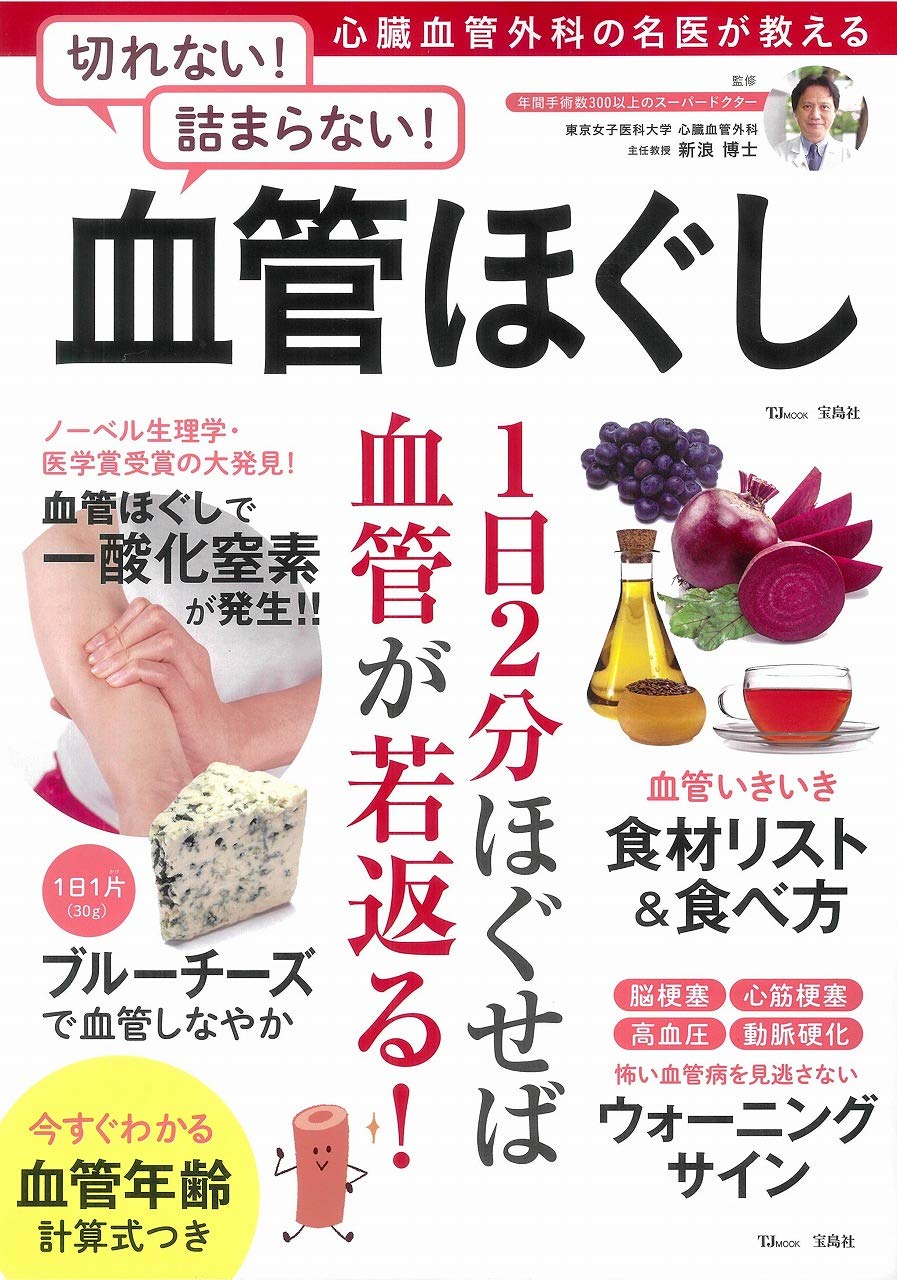

心臓血管外科の名医が教える 切れない 詰まらない 血管ほぐし Tjmook Amazon Com Books